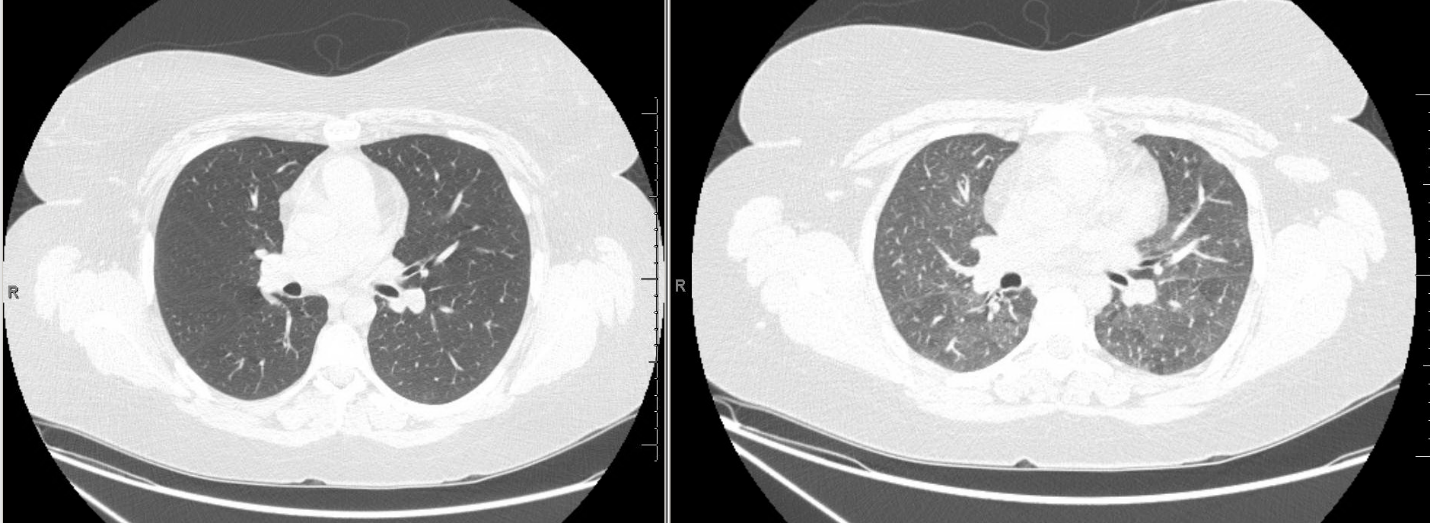

High resolution CT Imaging

Inspiratory (left) and expiratory (right) images were obtained. Representative images from approximately the same cross sectional level are shown.